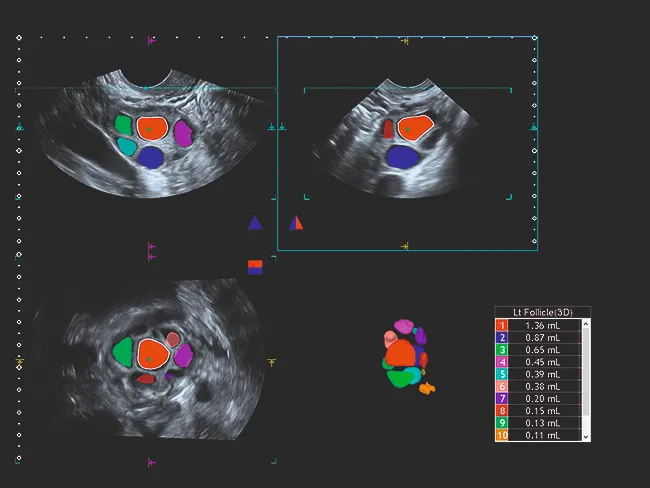

Как занятый врач, так и пациент могут воспользоваться 2D-визуализацией высокого разрешения и объемным ультразвуковым исследованием. Комплексный пакет объемной визуализации Aplio расширяет ваши диагностические возможности и выходит на новый уровень визуализации благодаря исключительному качеству изображения и бескомпромиссному рабочему процессу.

Широкий спектр опций MultiView позволяет получать поперечные срезы с высоким разрешением, помогая лучше понять анатомические взаимосвязи или степень данного поражения.